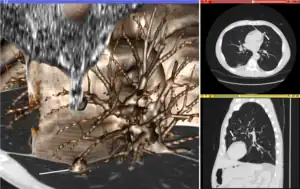

Visualization plays several key roles in Medical Image Computing. Methods from scientific visualization are used to understand and communicate about medical images, which are inherently spatial-temporal. Data visualization and data analysis are used on unstructured data forms, for example when evaluating statistical measures derived during algorithmic processing. Direct interaction with data, a key feature of the visualization process, is used to perform visual queries about data, annotate images, guide segmentation and registration processes, and control the visual representation of data (by controlling lighting rendering properties and viewing parameters). Visualization is used both for initial exploration and for conveying intermediate and final results of analyses.

The figure "Visualization of Medical Imaging" illustrates several types of visualization: 1. the display of cross-sections as gray scale images; 2. reformatted views of gray scale images (the sagittal view in this example has a different orientation than the original direction of the image acquisition; and 3. A 3D volume rendering of the same data. The nodular lesion is clearly visible in the different presentations and has been annotated with a white line.